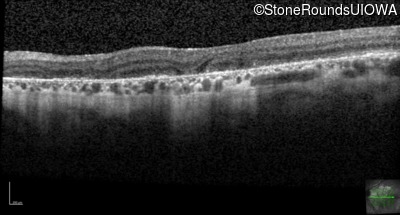

Age at visit: 55 years

Age at visit: 56 years

Age at visit: 57 years

Age at visit: 57 years (Visit 2)

Age at visit: 57 years (Visit 3)

Age at visit: 57 years (Visit 4)

Age at visit: 58 years

Age at visit: 58 years (Visit 2)

Age at visit: 59 years

Age at visit: 59 years (Visit 2)

Age at visit: 60 years

Age at visit: 60 years (Visit 2)

Age at visit: 61 years

Age at visit: 62 years

Age at visit: 62 years (Visit 2)

Age at visit: 63 years

Age at visit: 63 years (Visit 2)

Age at visit: 65 years

Age at visit: 66 years

Age at visit: 67 years